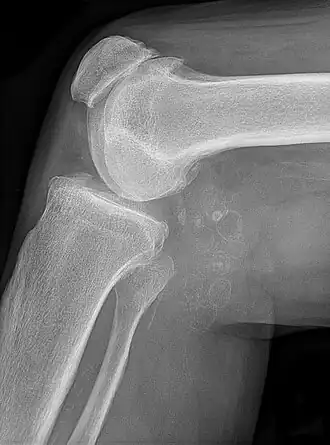

Chondromatose synoviale avec chondromes multiples dans le kyste de Baker, liés à une gonarthrose.